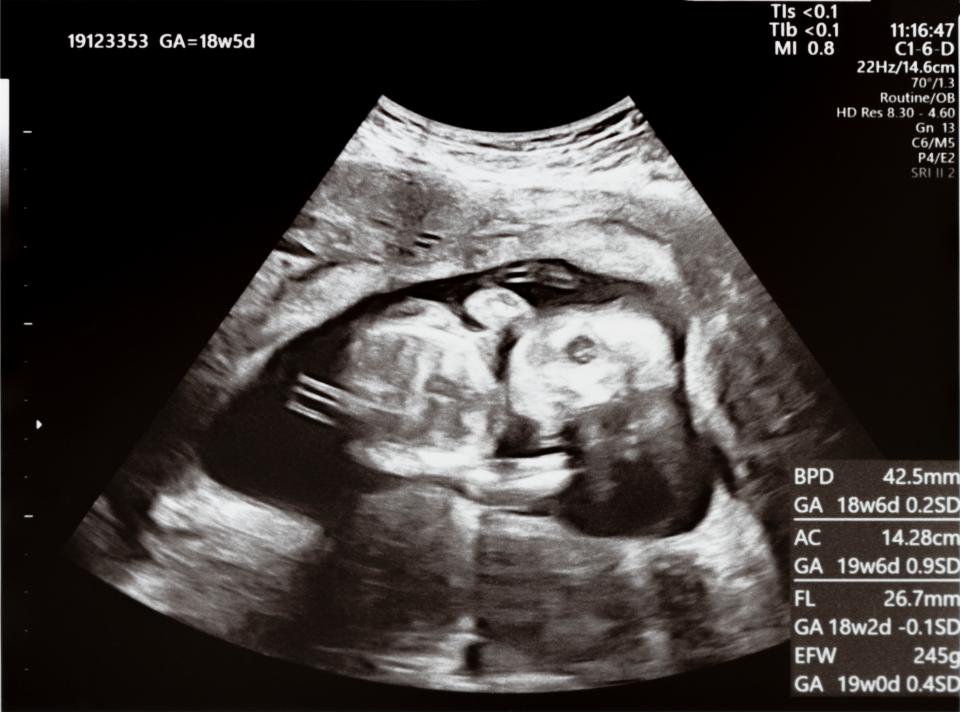

とはいえ、妊娠が判明した時点で服用は中止し、医師に相談することが大切です。 今後の経過をしっかりと見守るためにも、受診のうえで胎児の状態を確認しましょう。